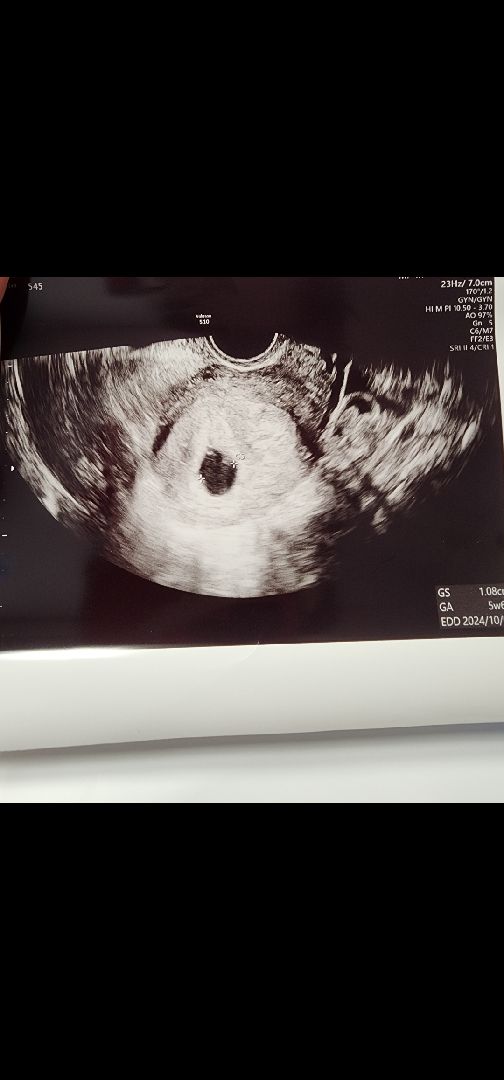

3์ผ์ ๋ง ํด๋ ์๊ธฐ์ง 0.6mm์ด์๋๋ฐ ๋ฐฐ์ฝ์ฝ์ด ์ฌ๋ผ์ง๊ฒ๊ฐ์์ ์ง๊ทผ์ฒ๋ณ์๊ฐ๋๋ 1cm๊น์ง์ปค์ง๊ณ ๋ํฉ๋๋ดค์ด์~! ์ค๋ ๋๋๋ฉด ์ฌ์ฅ์๋ฆฌ๋ค์ ์ ์๋คํ๋๋ฐ ๋นจ๋ฆฌ ๊ทธ๋ ์ด์์ ์ข๊ฒ ๋ค์ฉ!